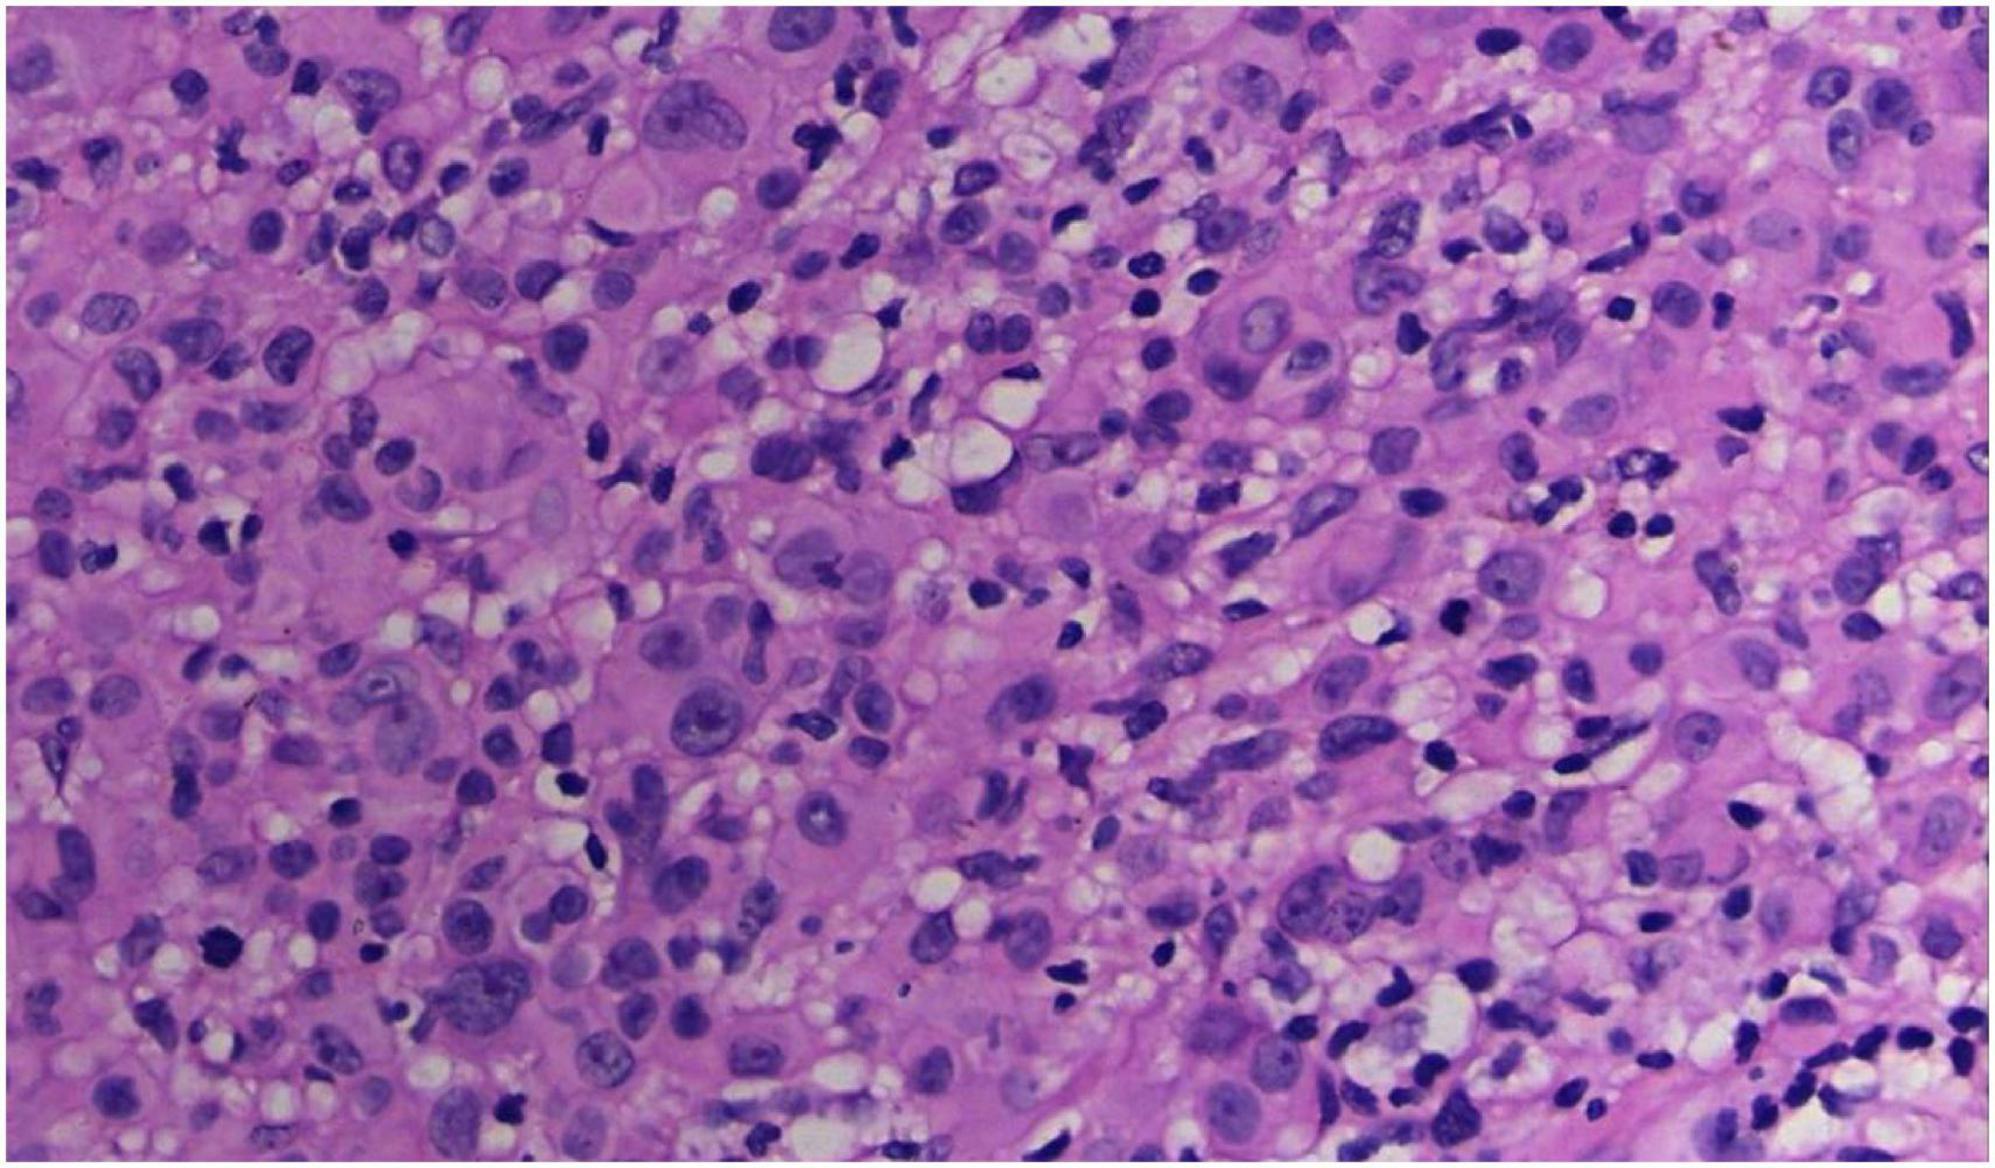

FIGURE 3

The tumor cells were polygonal, either round or oval, which had abundant cytoplasm filled with eosinophilic granules, and were stained pale pink. The nuclei were small, hyperchromatic and centered, with few mitotic figures, and multiple nuclei were observed in some tumor cells (Hematoxylin and Eosin Stain, × 200).

No abnormalities were found upon routine blood and urine tests, coagulation function test and syphilis/HIV screening. Chest X-ray and abdominal B-ultrasound also revealed no abnormalities. Cutaneous histopathology: epidermal processes disappeared, and the dermis was diffusely infiltrated by substantial tumor cells that were in the nested or clumpy form. These polygonal tumor cells were round or oval, which had abundant cytoplasm filled with eosinophilic granules, and were stained pale pink. The cellular nuclei were small, hyperchromatic and centered, with few mitotic figures, and multiple nuclei were observed in some tumor cells. Immunohistochemistry: S-100 (+), CD56 (−), NSE (−), vimentin (+), CD68 (+), Ki-67 (+), cell proportion: 5%, p53 (−), SAM (+−). CK (−), calponin (−), CD163 (−), desmin (−), CD34 (−), CD45 (−), CD30 (−), SMA (1A4) (−), ALK (−), HMB45 (−), melan-A (−).

The dermis was diffusely infiltrated by substantial tumor cells that were in the nested or clumpy form. These polygonal tumor cells were round or oval, which had abundant cytoplasm filled with eosinophilic granules.

Diagnosis of GCTs is based primarily on the histopathological examination. Regarding the histopathological features of GCTs, the lesions are located mainly in the dermal, subcutaneous or submucosal tissue, and the tumor cells mostly exhibit banded or nested growth. The tumor cells are large, polygonal and filled with fine eosinophilic granules in the cytoplasm. The cellular nuclei are small and centered, which are either round or oval. Common immunohistochemical markers: S-100 protein (+), NSE (+), CD68 (+), CK (−), SMA (−), GFAP (−), etc.